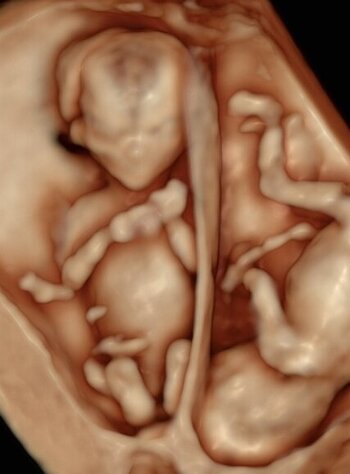

Zwillingsschwangerschaft (dichorial) in der 3D-Darstellung)

Die 3D-Sonographie erlaubt uns in der Pränataldiagnostik und Schwangerenambulanz die dreidimensionale Darstellung von Strukturen. Bestimmte Auffälligkeiten wie eine Lippen-Kiefer-Gaumen-Spalte oder andere Fehlbildungen können den werdenden Eltern besser aufgezeigt werden. Zudem ist eine dreidimensional dargestellte intakte Struktur im Zweifelsfall auch beruhigend.

Zudem hat die vorgeburtliche 3D-Untersuchung den Vorteil, dass die sehr plastische Darstellung die Mutter-Kind-Bindung verstärkt.

Die Durchführbarkeit hängt im Wesentlichen von den zugrundeliegenden Untersuchungsbedingungen ab. So muss genügend Fruchtwasser vorhanden und die Kindslage günstig sein. Auch Schwangerschaftsalter und die mütterliche Konstitution spielen eine zentrale Rolle.

Allerdings kann der 3D-Ultraschall die konventionelle 2D-Sonografie nicht ersetzen, sondern lediglich ergänzen und sollte daher nicht isoliert eingesetzt werden. 4D-Sonografie bedeutet 3D-Ultraschall am bewegten Bild. Stellen Sie es sich als eine Art 3D-Untersuchung in live vor.